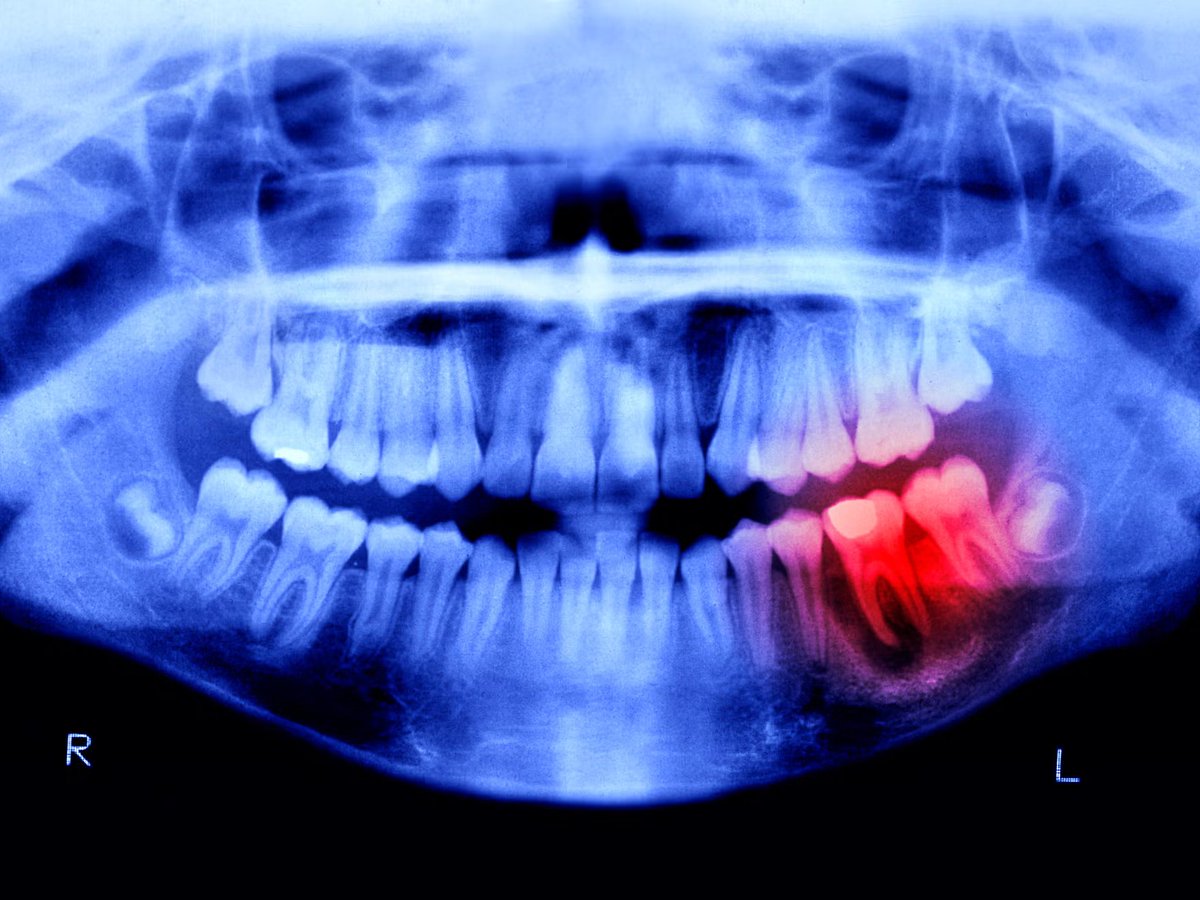

日本“牙齿再生药”开启人体试验,目标2030年上市 日本科学家正在推进一项听起来像科幻电影的突破:让人类重新长出牙齿。这项由大阪北野医院和京都大学合作研发的“牙齿再生药”,已于2024年9月正式开启人体临床试验。